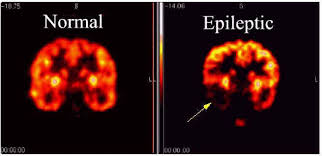

Epilepsy is a neurological disorder